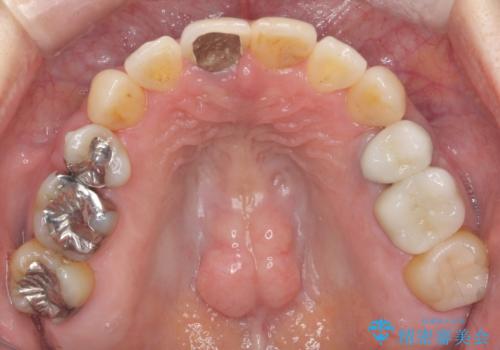

50代女性 八重歯を矯正治療 歯並びの中等度のがたつき

- ワイヤー矯正

- 八重歯の矯正を希望されて来院。

歯は入りきらないため、通常の抜歯矯正を行いました。

歯がご年齢的に動きにくいため、被せ物のやり替えを含めて治療期間の短縮を図りました。

矯正治療自体は2年半、虫歯治療等で1年ほどかかっています。

詰め物や被せ物のやり替えも併せて行っているため、治療期間を比較的短縮できました。